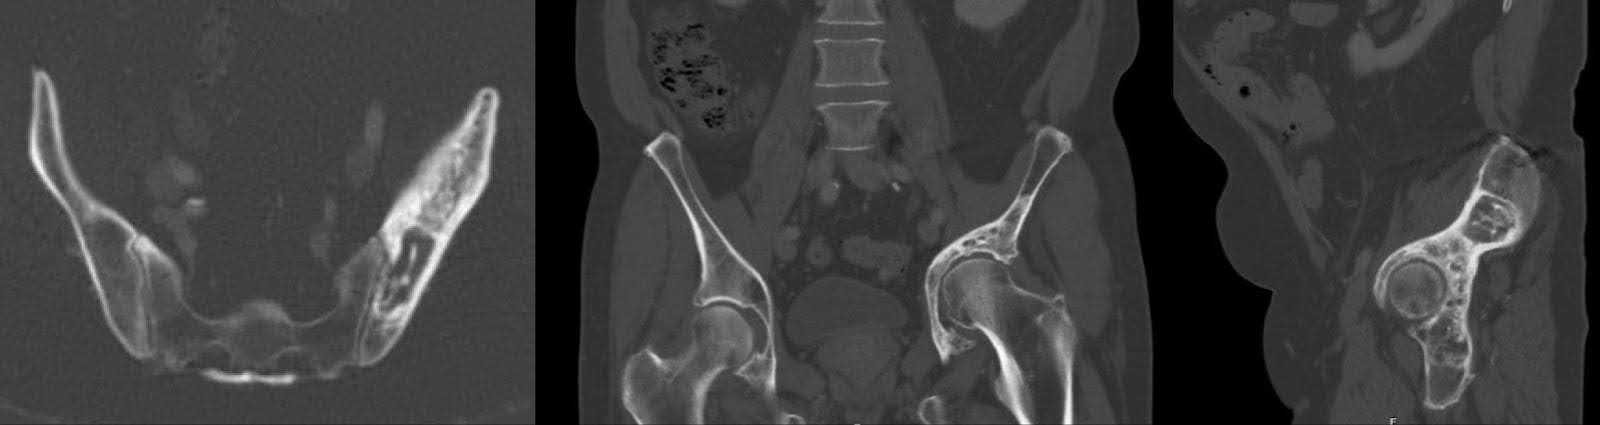

Subsequent X-ray imaging, conducted three months preoperatively, revealed no substantive change in the appearance of mixed sclerotic and lytic lesions within the left hemipelvis, in keeping with treated lymphoma. This was accompanied by acetabular remodeling and cranial migration of the proximal femur, with degenerative changes in the left hip joint (Figure 1). Computed tomography (CT) findings aligned with those on X-ray, affirming the observed pathology (Figure 2).

Figure 2. Axial, coronal, and sagittal views of CT of the pelvis three months prior to surgery. Mixed sclerotic/lytic lesion of the acetabulum redemonstrating treated lymphoma. Collapse of the acetabular roof and migration of the proximal femur into the supra-acetabular area with protrusion.